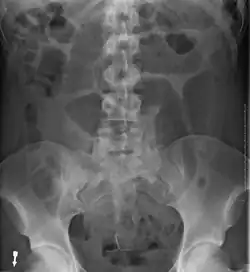

Plain X ray of a cecal volvulus -